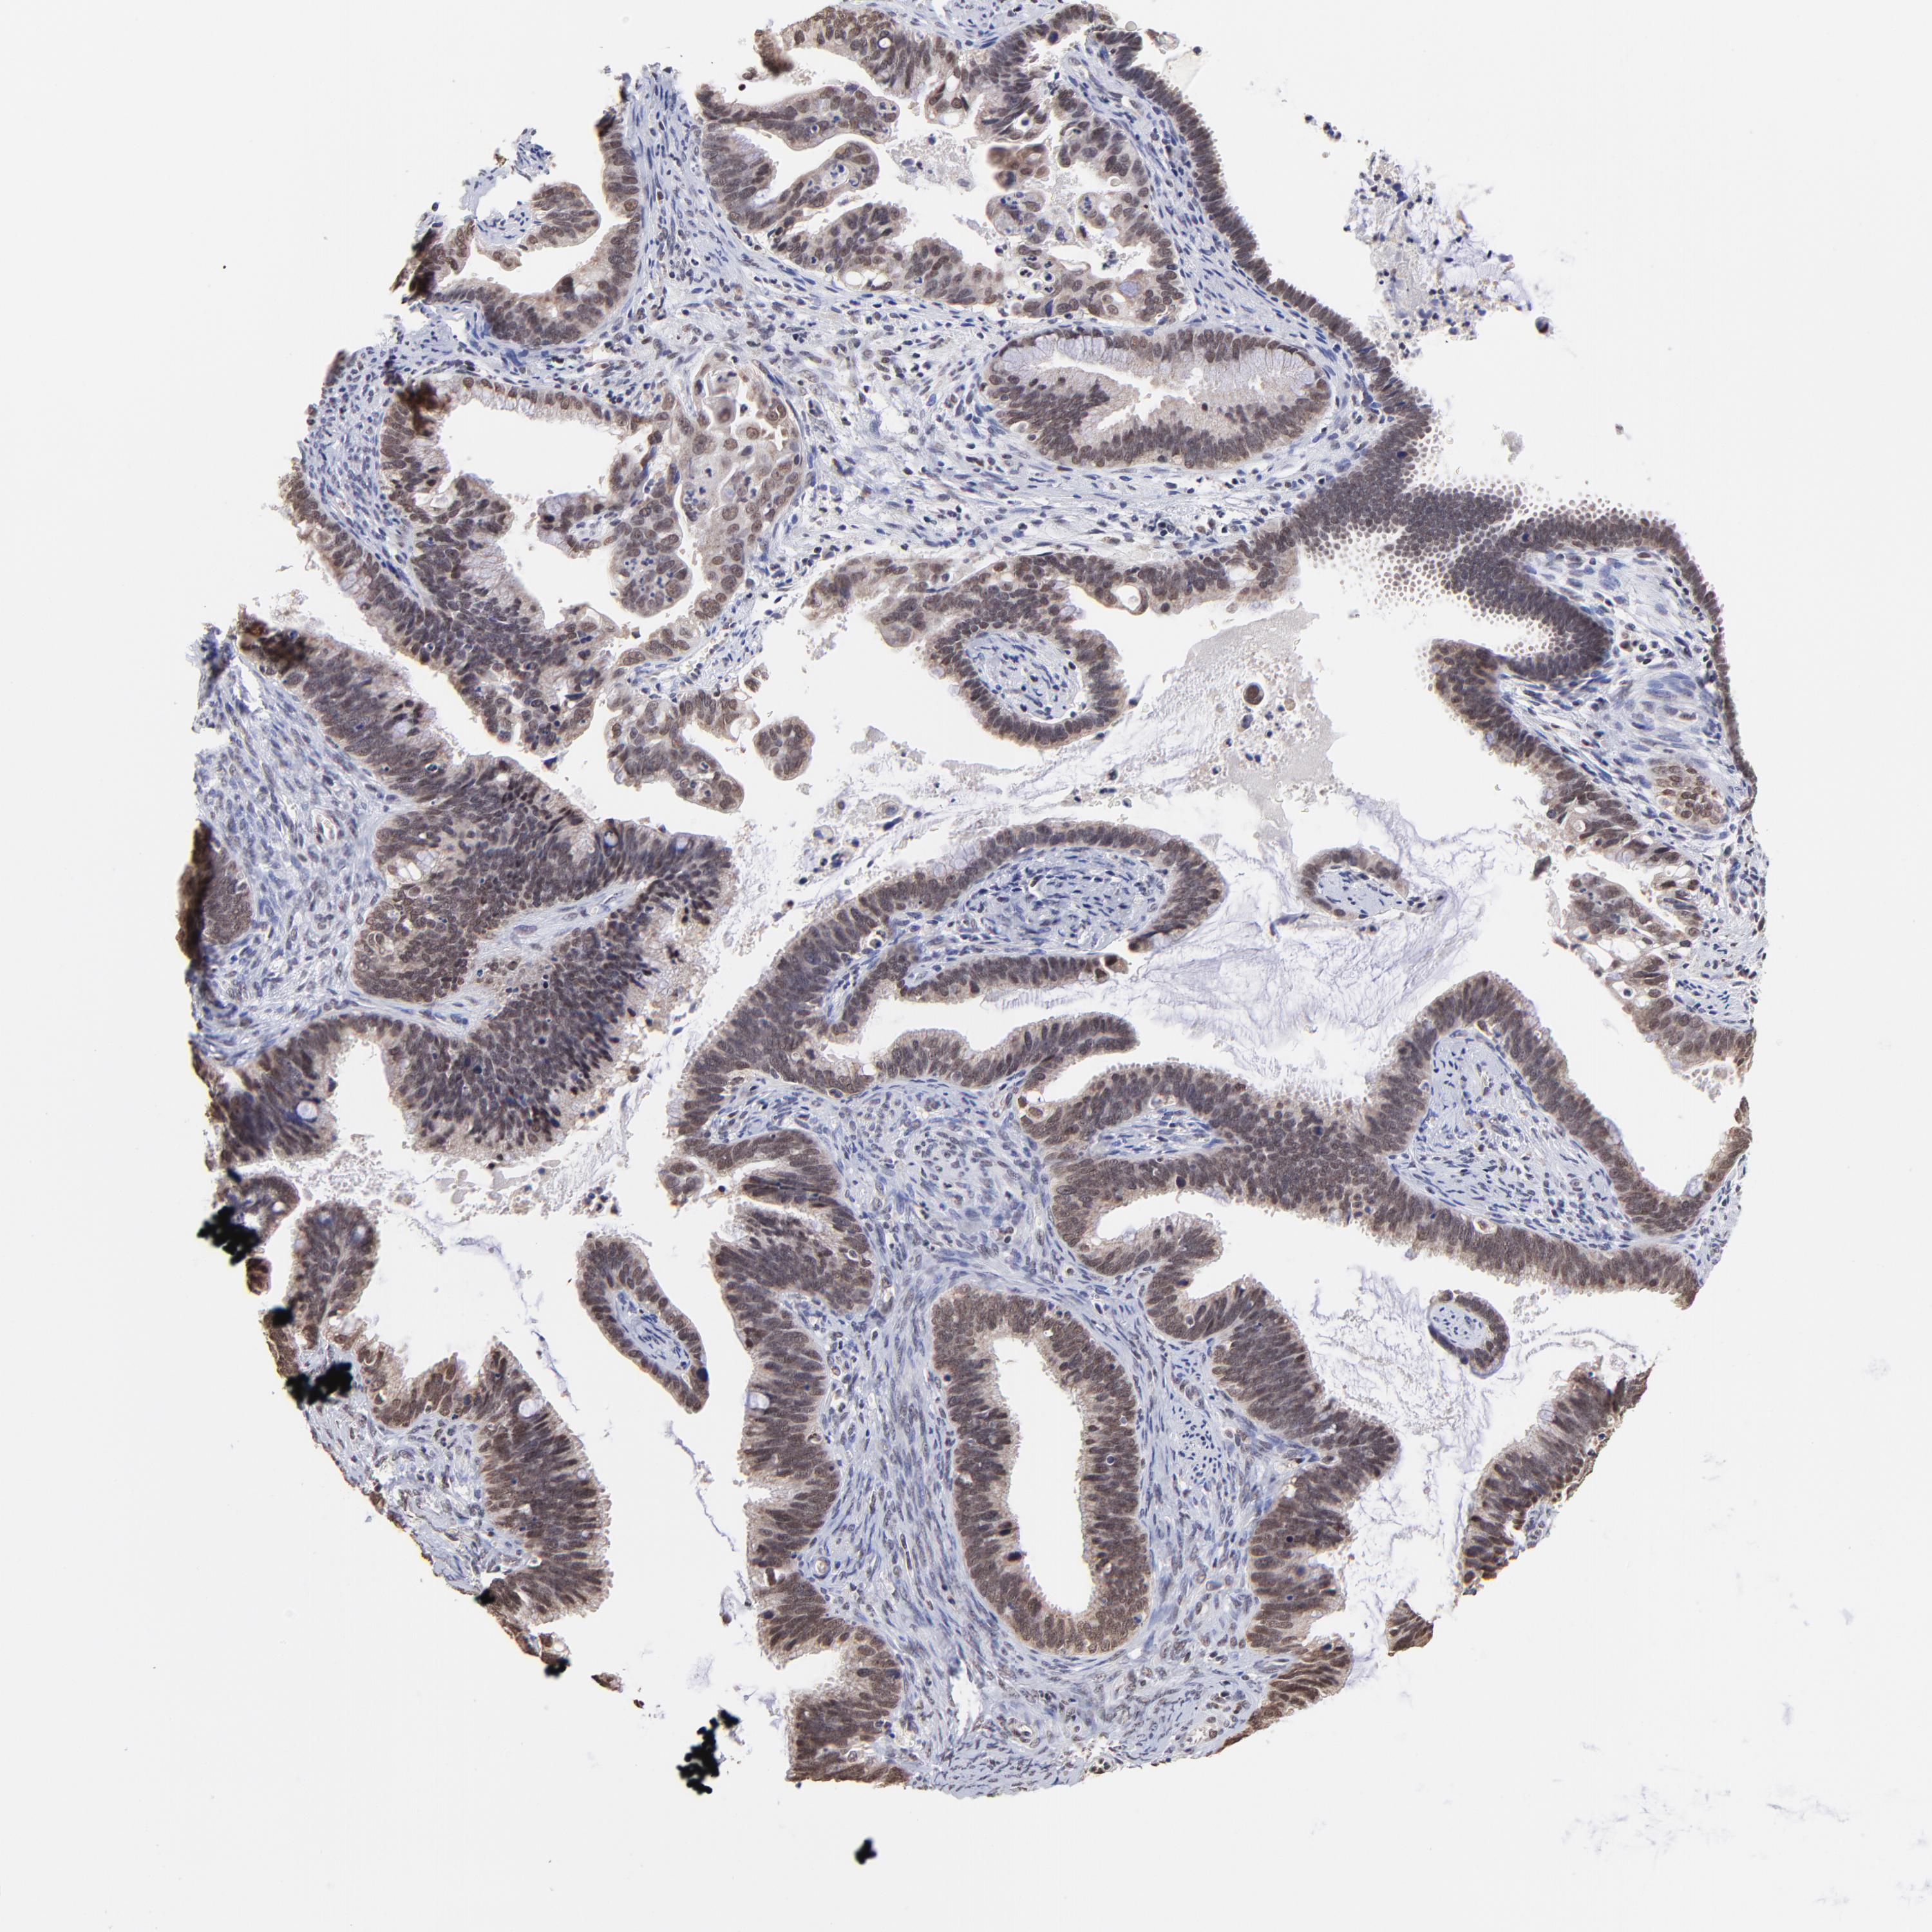

CERVICAL CANCER - Protein expressioni

A mouse-over function shows sample information and annotation data. Click on an image to view it in a full screen mode. Samples can be filtered based on level of antibody staining by selecting one or several of the following categories: high, medium, low and not detected. The assay and annotation is described here.

Note that samples used for immunohistochemistry by the Human Protein Atlas do not correspond to samples in the TCGA dataset.

Antibody stainingi

Antibody staining in the annotated cell types in the current human tissue is reported as not detected, low, medium, or high, based on conventional immunohistochemistry profiling in selected tissues. This score is based on the combination of the staining intensity and fraction of stained cells.

Each image is clickable and will lead to virtual microscopy that enables deeper exploration of all samples and also displays staining intensity scores, fraction scores and subcellular localization as well as patient and tissue information for each sample.

Antibody HPA003142

Staining

High

Medium

Low

Not detected

Intensity

Strong

Moderate

Weak

Negative

Quantity

>75%

75%-25%

<25%

None

Location

Nuclear

Cytoplasmic/membranous

Cytoplasmic/membranous,nuclear

Adenocarcinoma, NOS

Squamous cell carcinoma, NOS